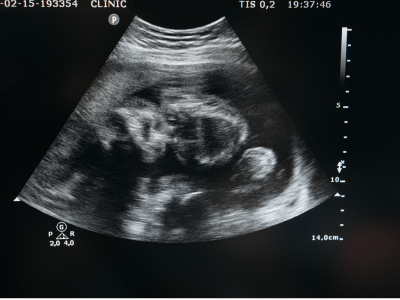

아이를 위한 첫 보험, 태아보험. 하지만 100세 만기 vs 30세 만기 중 어떤 것을 선택해야 할지 고민이 되시나요?

태아보험은 출생 전부터 태아와 신생아 시기에 발생할 수 있는 의료비를 보장하는 보험이지만,

만기 기간에 따라 보험료와 보장 내용이 크게 달라집니다.

이번 글에서는 태아보험 어린이보험 100세 만기와 30세 만기의 차이점, 장단점, 가입 시 고려할 사항을 상세하게 비교해 보겠습니다.